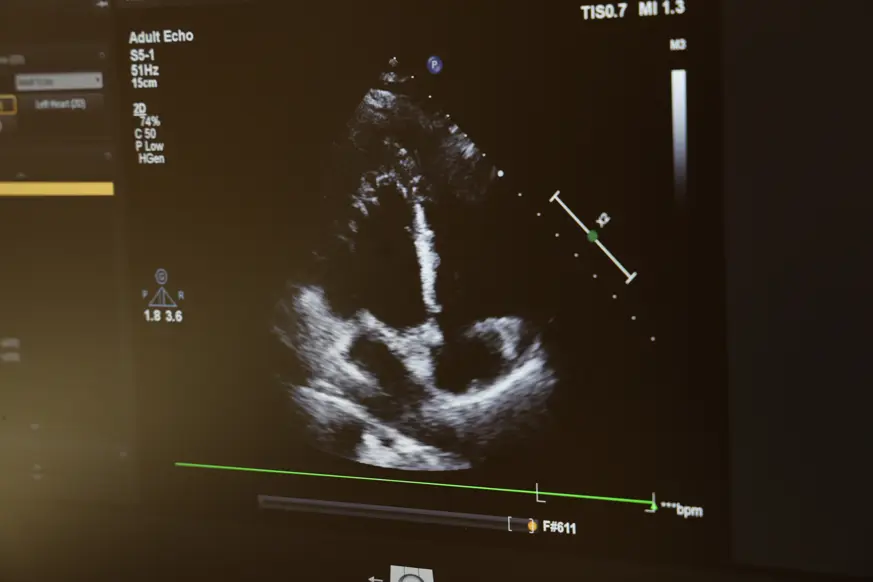

Gerekli teşhis EKG çekilerek bazen 24 saatlik cihazlarla tanının belirlenmesi lazım. Bütün bunlara rağmen çarpıntı olan kişilerin ritim bozukluğu bazen 24 saatlik EKG ile de tespit edilmeyebilir.

Bunun ritim anjiyosu dediğimiz EPS ile tanı konulabilir ve aynı zamanda bu esnada tedavisi de yapılabiliyor. Ritim bozukluğunun çoğu ilaç tedavi ile düzeltilebilir. Bir kısmı da yakma tedavisi dediğimiz ablasyon tedavisi ile çarpıntıların büyük bir kısmı tedavi edilebilmektedir.”